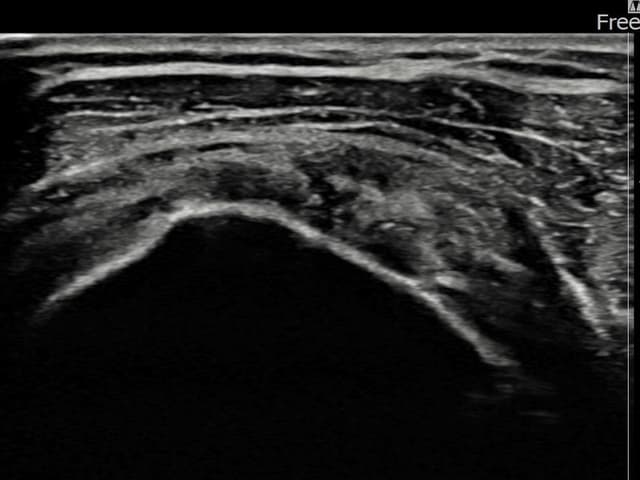

左侧 冈上肌腱 关节面侧部分撕裂

3.5mm × 3.1mm (부분파열)

左侧 冈上肌腱 附着部部分撕裂

5mm × 3mm (肌腱厚度约25%缺损)